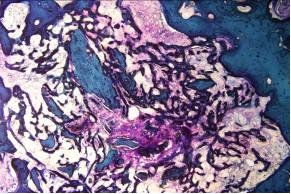

Presso il Settore Istologia vengono allestiti preparati istologici di vari tessuti sia decalcificati che mineralizzati. E possibile lo studio di tessuto osseo in presenza di impianti protesici per analisi di osteointegrazione e reazione tessutale agli impianti. I campioni e le sezioni istologiche vengono sottoposti ad ulteriori valutazioni quantitative quali ad esempio l’istomorfometria e la microdurimetria.

Nel Settore di Istomorfometria, Microarchitettura Biomateriali Osso vengono eseguite misurazioni istomorfometriche di biomateriali, scaffolds e tessuti biologici attraverso l’utilizzo di programmi per l’analisi di immagine per studiare e misurare la morfologia di tessuti e materiali, la reazione tessutale agli impianti, le proprietà osteoinduttive, osteoconduttive ed osteointegrative di biomateriali, protesi o dispositivi per l’ingegneria tessutale, la fisiopatologia e la riparazione dei tessuti dell’apparato muscolo scheletrico a seguito di patologie o trattamenti innovativi. Tecniche quantitative istomorfometriche sia statiche che dinamiche (attraverso marcatori fluorescenti) vengono adottate per misurare reazione infiammatoria, spessore e qualità della capsula fibrosa attorno a biomateriali impiantati nei tessuti, la percentuale di osteointegrazione dei biomateriali (“affinity index”, “bone ingrowth” e “mirror area”), la percentuale di riparazione tessutale a seguito di una lesione utilizzando score istomorfometrici e misurando vari parametri a seconda del tessuto di interesse. Per il tessuto osseo si segnalano: numero, spessore, separazione delle trabecole, spessore osso corticale, quantità di osso neoformato, volume di osteoide, indici dinamici di formazione e mineralizzazione ossea e la vascolarizzazione tessutale. Per il tessuto cartilagineo a seconda della patologia acuta o cronica, oltre all’impiego di affidabili score istomorfometrici semiquantitativi, si utilizzano misure su spessore cartilagine articolare, indice di fibrillazione, spessore ed analisi dell’osso sub condrale.